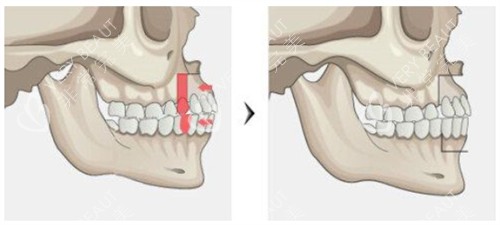

我查了半年资料,问过3家医院。有网友分享说,双颚手术对医生颌面解剖功底要求极高,普通整形医生未必能做。直到在广大面诊罗延平医生——他拿3D头模给我演示:你的下颌骨过度发育,上颌后缩,需要通过双颚截骨调整咬合,同时改善面型。他办公室墙上挂着200+台正颌实例,有位和我情况类似的姐姐术后半年的对比照,下颌线条流畅得像天生的。

朋友小琪也在另一家医院做过轮廓手术,她说:你这种咬合问题得找能做正颌的医生,普通磨骨解决不了根本。罗医生的方案里,除了调整骨头位置,还详细标注了颏成型的衔接设计,说要避免阶梯感,这点让我特别安心。

手术当天早8点进准备室,护士给我戴头套时轻声说:罗主管今天推了其他手术,专门给你做。进手术室看到罗医生在调试四维头影测量仪,电脑屏幕上是我术前拍的CT重建图,他指着下颌角位置说:等会这里截3mm,那边2.5mm,对称度能控制在0.5mm内。麻醉师让我深呼吸时,我突然闻到罗医生白大褂上淡淡的消毒水味——和我爸当外科医生时的味道好像,莫名就踏实了。